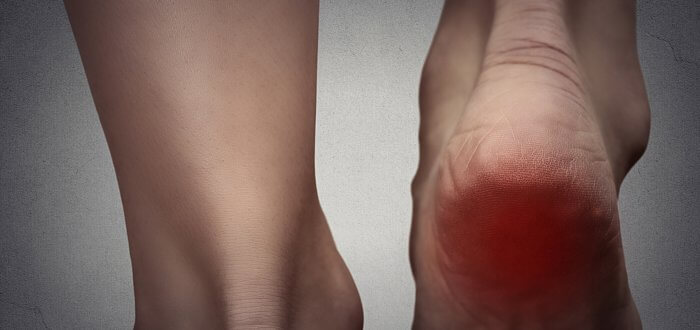

El espolón es una exostosis es decir una proliferación ósea que aparece en la parte anterior del calcáneo, en el talón.

El síntoma principal es el dolor en el talón (talalgia), normalmente está acentuado en los primeros pasos del día y va cediendo a lo largo de la mañana, puede incrementarse también durante largas caminatas.